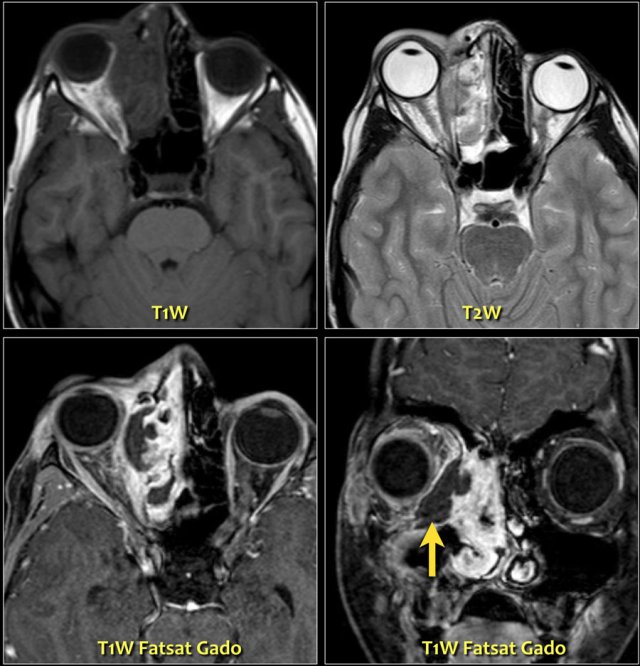

On the left images of an adult with an ocular mass.

The most common intraocular lesion in an adult is melanoma (as in this case).

Number two is metastases and others like hemangioma, leiomyoma and osteoma are uncommon.